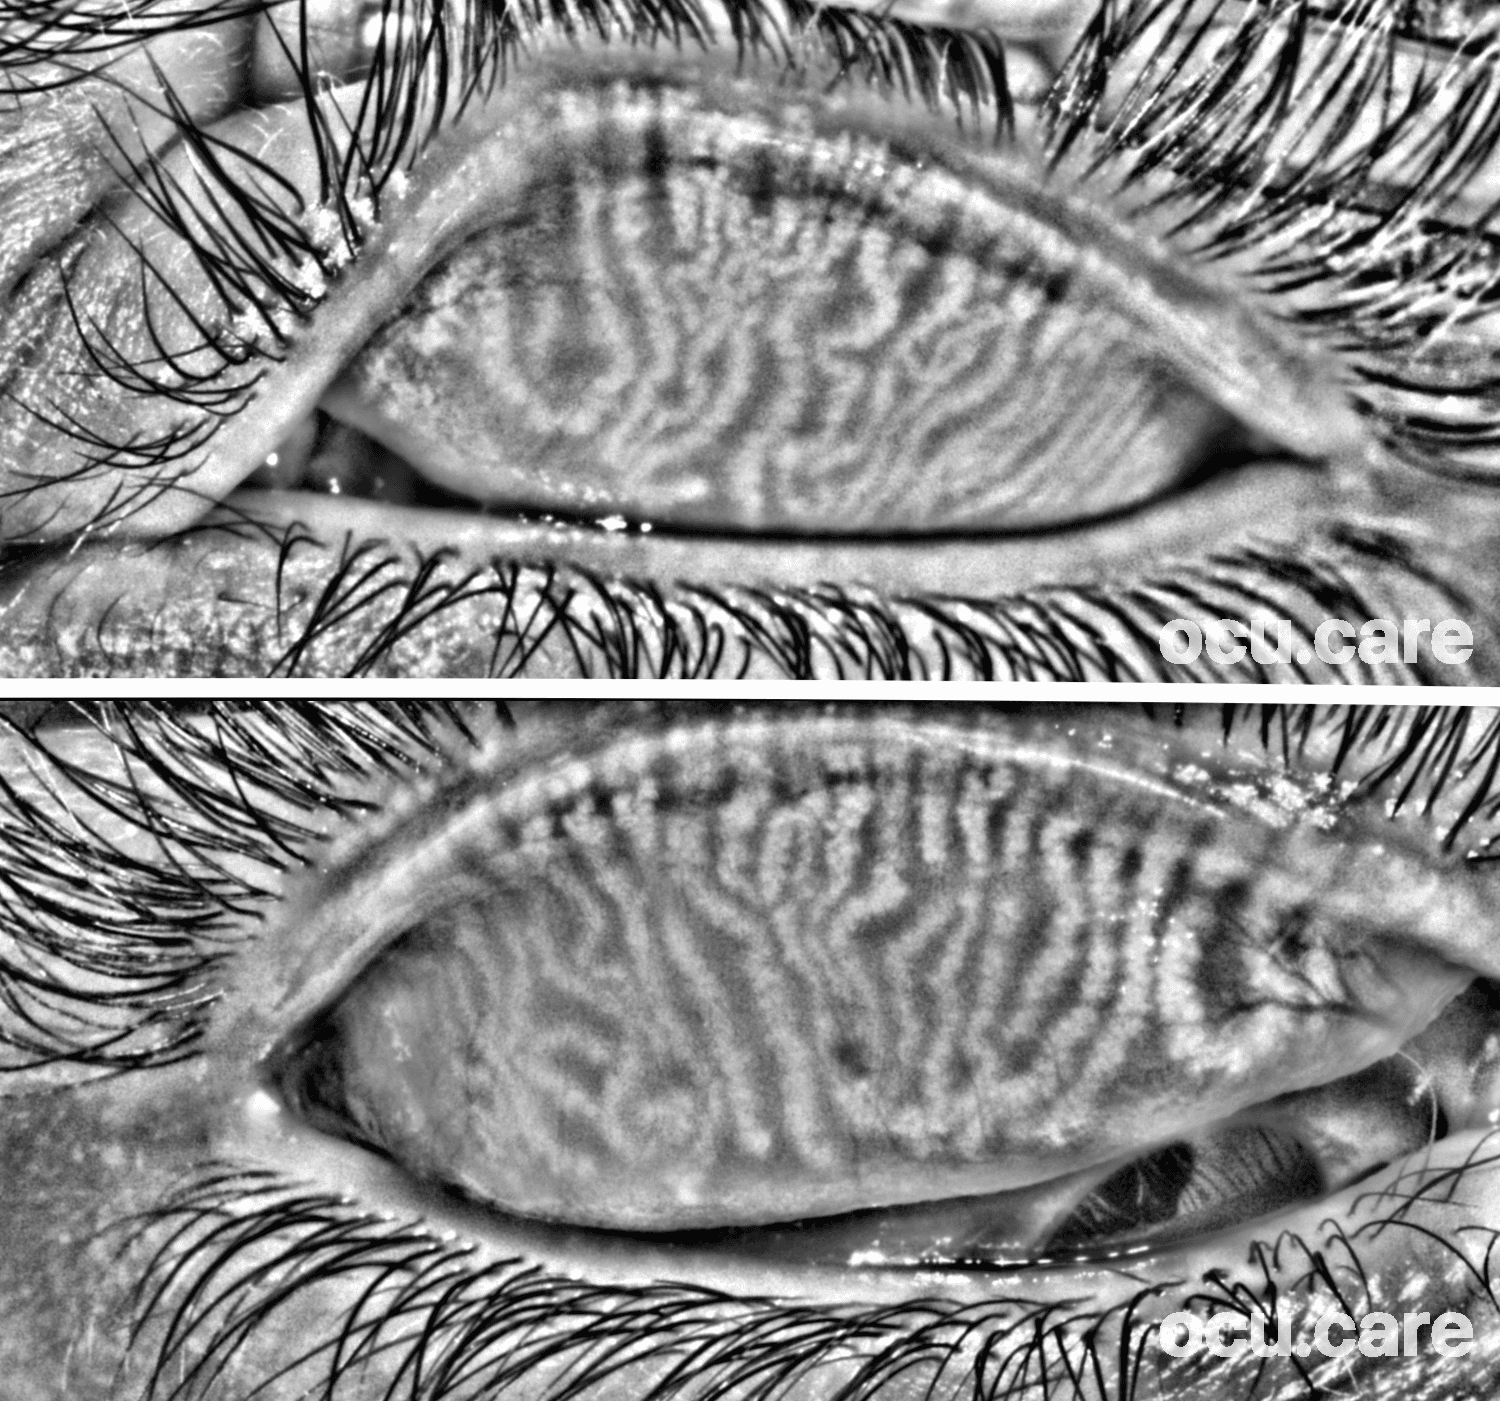

Thi meibography image shows the upper-lid meibomian glands of an 18-year-old male with no prior ocular disease who has worn ortho-k lenses for eight years. Despite being entirely asymptomatic, the glands demonstrate clear tortuosity.

Evidence suggests that long-term orthokeratology wear may influence meibomian gland morphology and tear-film stability—often without overt symptoms. Such changes can develop silently.